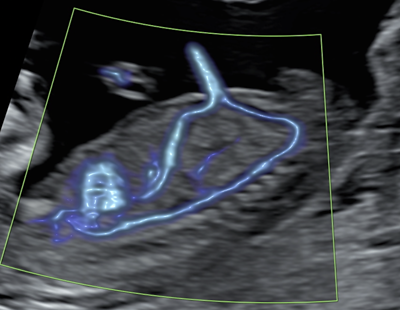

Échographie du troisième trimestre

Le but de l’examen du troisième trimestre (après 26 semaines) est principalement d’évaluer le bien être de votre fœtus. Il peut être indiqué dans de nombreuses situations telles que :

• Mesure des flux Doppler